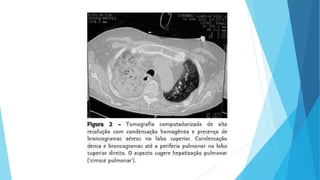

Características da Imagem